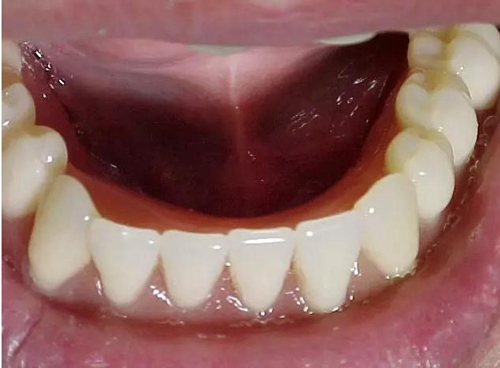

【牙科干貨】作為牙醫(yī)或技師,你需要知道如何做好全口義齒。

臨床上,很多的牙科醫(yī)生對(duì)于全口義齒不感興趣,因?yàn)槿诹x齒整個(gè)操作的過(guò)程相當(dāng)復(fù)雜,程序相當(dāng)繁瑣,患者就診的時(shí)間相當(dāng)長(zhǎng),復(fù)診的次數(shù)相當(dāng)多,而且相當(dāng)不掙錢。然而,中國(guó)社會(huì)老齡化問(wèn)題日趨嚴(yán)重,全口義齒需求也在逐年上升,作為一名牙科醫(yī)生,你至少得知道它是如何做成的。那么如何做好一副全口義齒呢?

在排列全口義齒前牙時(shí),首先考慮的是對(duì)恢復(fù)患者面容的作用。選牙時(shí)要考慮人工牙的大小、顏色、形態(tài)、以及和口唇部的協(xié)調(diào)程度。

后牙主要以恢復(fù)患者的咀嚼功能為主,排牙時(shí)要根據(jù)患者牙槽嵴的近遠(yuǎn)中長(zhǎng)度、牙槽嵴的吸收程度以及上下頜弓的位置關(guān)系和頜間距離的高低來(lái)選擇后牙的合面形態(tài)和大小。